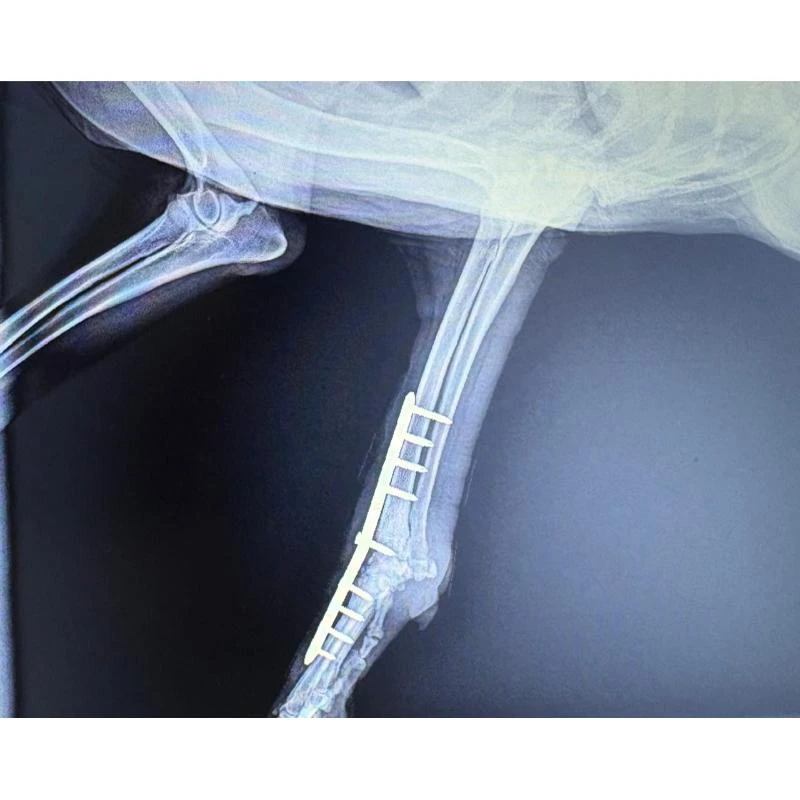

A realização de cirurgias em animais de estimação muitas vezes requer a utilização do raio x veterinário para auxiliar os profissionais durante o procedimento.

O exame de raio x permite uma visualização detalhada das estruturas internas do animal, auxiliando os veterinários na realização de cirurgias ortopédicas, odontológicas, de tecidos moles e emergenciais.

Planejar uma cirurgia com base em exames de raio x detalhados e em uma avaliação clínica minuciosa é fundamental para assegurar o sucesso do procedimento e a recuperação do animal.

O acompanhamento pós-operatório, aliado ao uso do raio x veterinário, assegura a segurança do paciente, previne complicações e promove uma reabilitação eficaz.